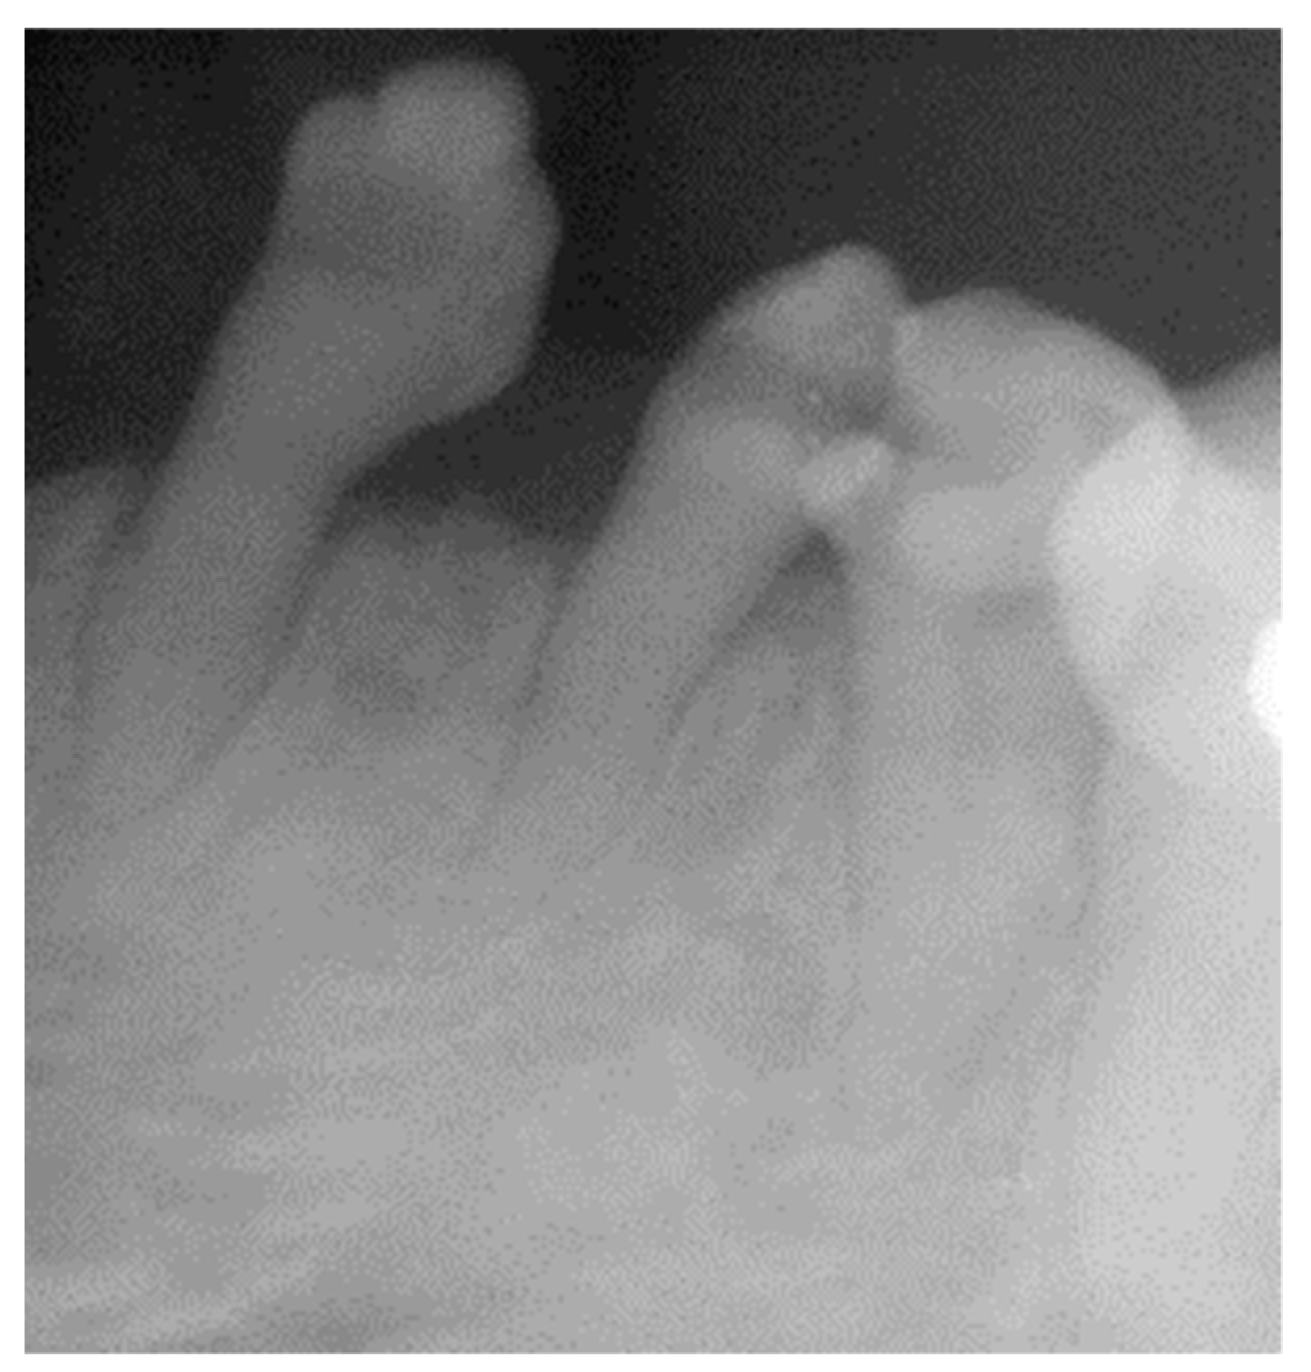

2.1. Clinical and Radiological Examination